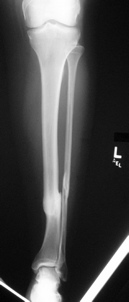

She complains of vague knee and back pain, which worsen with activity or prolonged standing. She is now 55, recently retired, but otherwise healthy and desires to hike, ski and exercise. She was injured 20 years earlier after being struck by a car. Other injuries included a ruptured spleen, and an early post-injury pulmonary embolism. Her tib-fib fx was treated in a cast. Her tibial shortening measures 2.5 cm on scanogram. Attached are today's films.